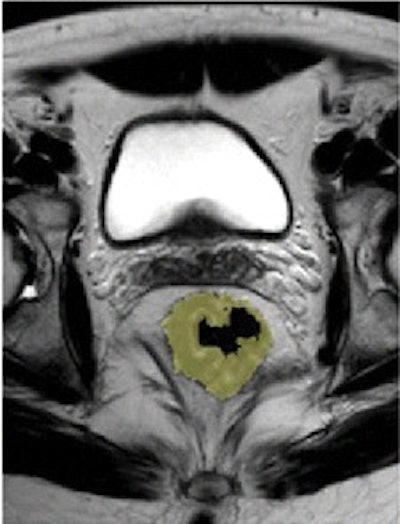

Pre- and post-treatment MRI was performed with a 1.5-tesla system (Intera R10, Philips Healthcare) using an eight-element pelvic phased-array surface coil. The subjects were imaged in the prone position after the placement of a thin rectal catheter in the rectum.

After initial localization imaging, researchers acquired MR images of the pelvis and rectum, with T2-weighted images obtained in the transverse, coronal, and sagittal planes during the scanning time of approximately 30 minutes.

Two radiologists, who were blinded to clinical information about each patient, independently evaluated the images obtained before and after chemotherapy and radiation treatment.

The MR images calculated the mean tumor volume was 58 cm3 ± 75 before chemotherapy/radiation treatment and 20 cm3 ± 31 after therapy. The mean tumor volume reduction ratio in all patients was 68% ± 23.

Downstaging occurred in 33 of the 58 patients (57%). The tumor volume reduction rates after chemotherapy/radiation treatment were significantly different between patients whose tumors were downstaged and those whose tumors were not downstaged (P < .0001). There also was no significant difference based on tumor location.